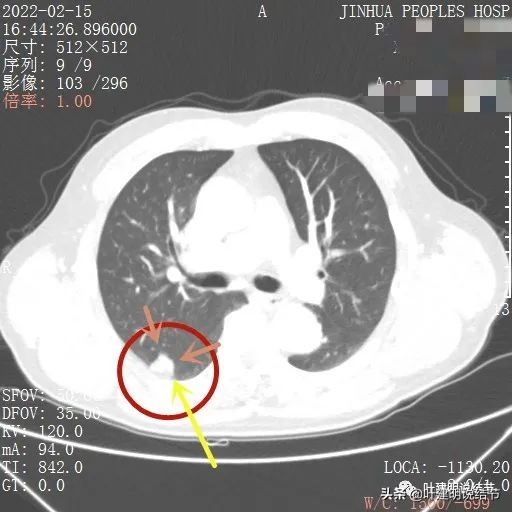

上图除了间隙以外,病灶有的地方有膨胀性,往外鼓出去一点(砖色箭头)

膨胀性以及与胸壁间隙

上图示病灶边缘毛糙(紫色箭头),以及与胸壁间的间隙存在(黄色箭头)

病灶边缘欠平整